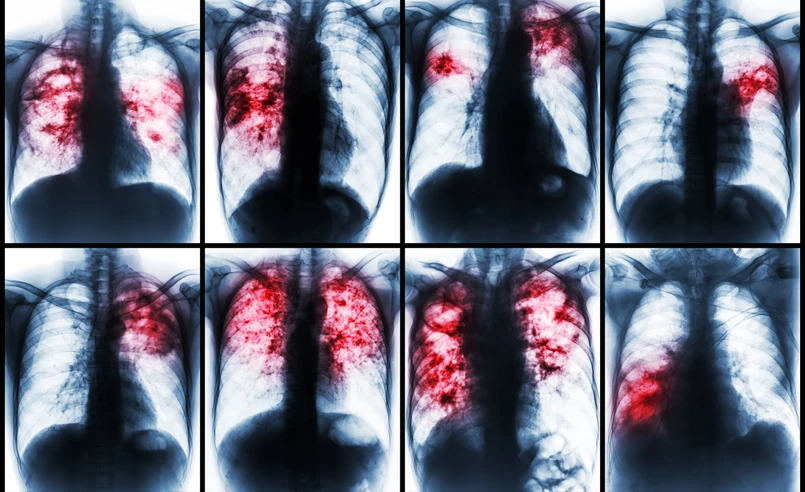

Ryzyko związane z niedokładnymi odpowiedziami może również narazić pacjentów na niebezpieczeństwo. Przykładowo Grok błędnie zidentyfikował złamany obojczyk jako zwichnięty bark. Lekarze stwierdzili również, że chatbot nie rozpoznał „podręcznikowego przypadku” gruźlicy, a w innym przypadku pomylił łagodną torbiel z jądrami.